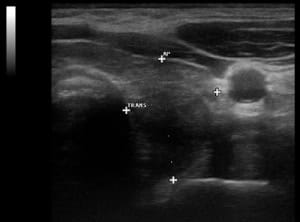

U.a. weisen Gewichtsveränderungen, Zyklusunregelmäßigkeiten und emotionale Instabilität auf Schilddrüsenfunktionsstörungen hin. Derbe Veränderungen in der Schilddrüse hingegen sind verdächtiger als weiche. Zu jeder Schilddrüsenuntersuchung gehört auch der Ultraschall von Schilddrüse und Halsweichteilen (Schilddrüsensonographie). Hierdurch lassen sich Größe und evtl. Veränderungen erkennen sowie relevante Strukturen in der vorderen Halsregion mit beurteilen, insbesondere Nebenschilddrüsen und Lymphknoten. Anhand des Schallmusters und des Durchblutungsmusters (Perfusion) lassen sich häufig bereits Krankheitsbilder festmachen.

So findet sich bei einer Autoimmunhyperthyreose (M. Basedow), einer zumeist schweren Form einer Schilddrüsenüberfunktion, eine ausgeprägte Echoarmut in Verbindung mit einer stark vermehrten Durchblutung des Schilddrüsengewebes. Von den Knoten verdienen solche mit Mikroverkalkungen und einer vermehrten Binnenperfusion verstärkte Aufmerksamkeit.